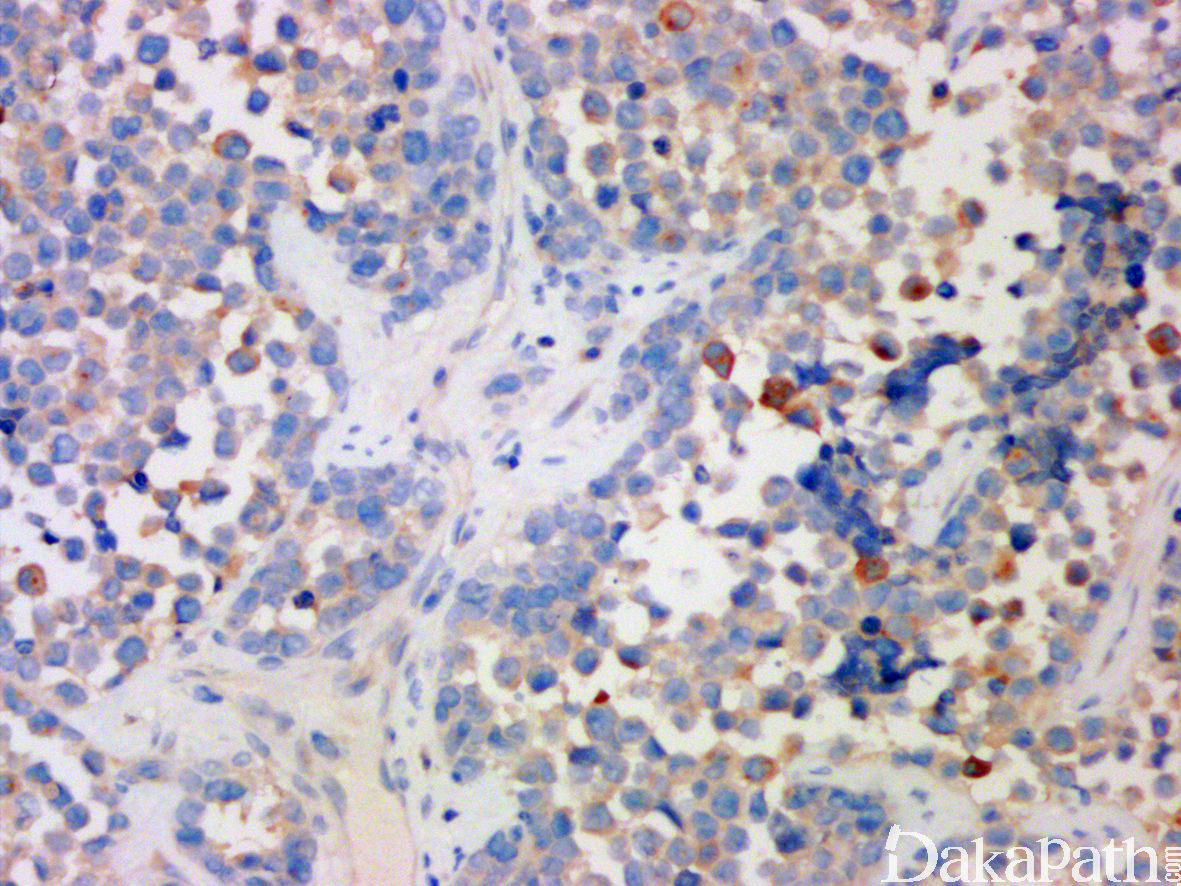

免疫组织化学染色:

显示瘤细胞核 myogenin、MyoD1. Desmin、HHF35 阳性,部分病例(腺泡状横纹肌肉瘤)可局灶表达 CK 和神经内分泌标记。